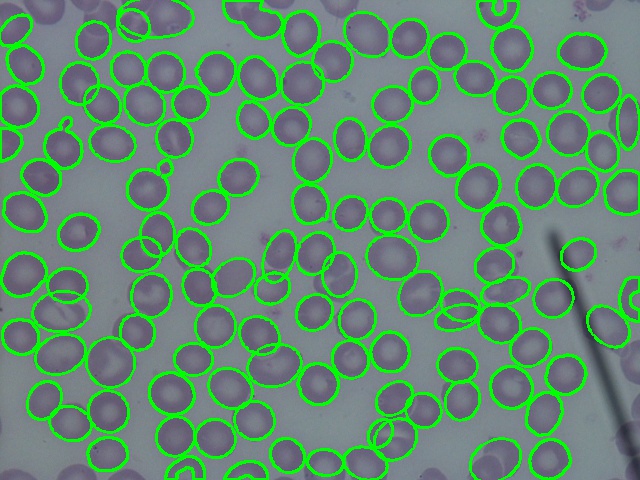

5.1 Overlapping cell separation

To evaluate the separation of the overlapping cells, we manually counted the overlapping contours that exclude cells on the border of the images and other artifacts, such as platelets, white blood cells, or microscope tools in the images. A total of 277 contours were found in 20 blood smear images, with an overall accuracy of 0.889. Most of the contours were two RBCs touching or overlapping with each other. The error in this method was mostly found on contours that had only one concave point. The results are summarized in Table 2, while blood smear images after segmentation are shown in Figure 8.